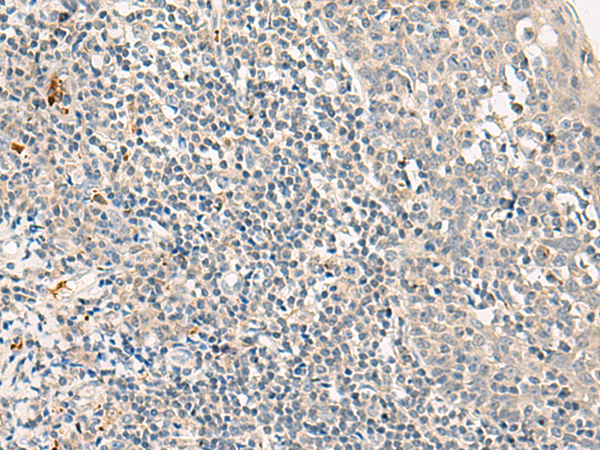

分类: 科研抗体货号: P06575别名: GPIV; GPVI; BDPLT11应用: WB,IHC反应种属: Human